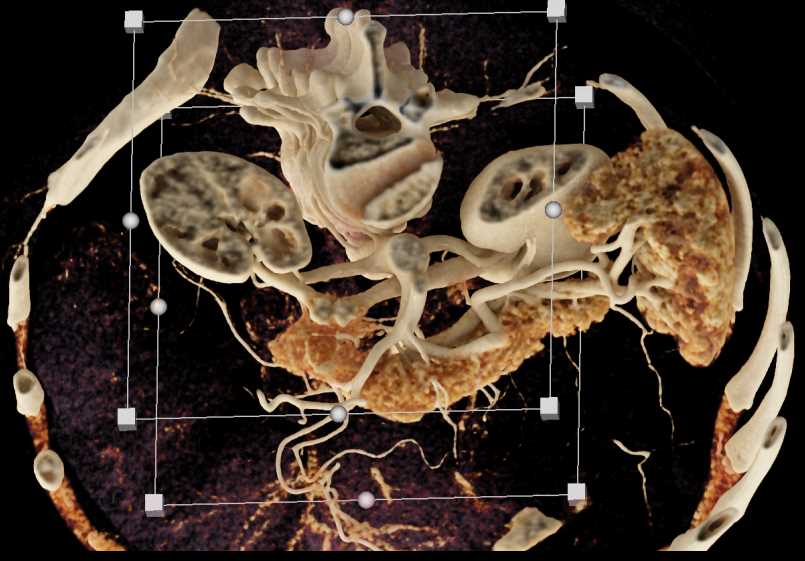

Subtle Neuroendocrine Tumor Body of Pancreas